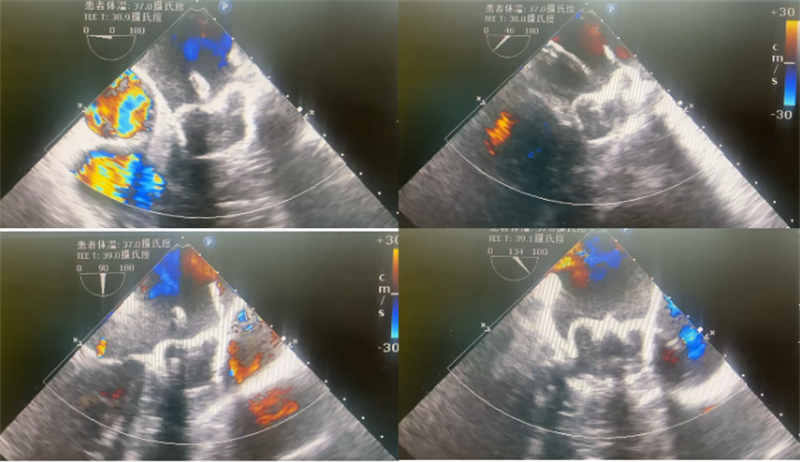

术前TEE排除心血耳栓测量

术前经食管超声(TEE)测量患者左心耳大小,确定Watchman尺寸:患者心耳呈菜花形态,开口呈椭圆形,直径为24-28mm,深度为21mm,预采用31mm或35mm WATCHMAN FLXTM封堵器进行封堵,压缩比控制在15%~25%。

超声显示:封堵器送入后,位置、锚定情况均良好,TEE135°下压缩比为14%,牵拉试验稳定,无残余分流,符合PASS原则,遂完全释放,复查造影提示封堵器封堵完全,最终手术顺利完成。

TEE下评估位置与残余分流

TEE下评估测量压缩比(14%)